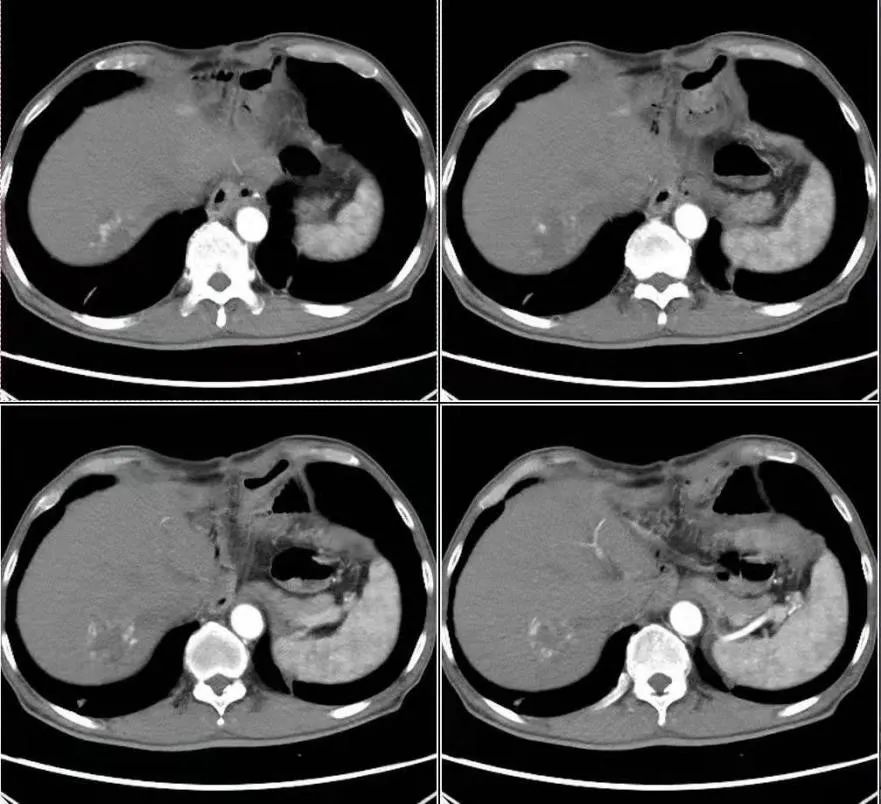

其实,在整个项目的实施过程中,有几个受试者的不良反应是相对来说比较大的,我总是跟患者沟通,或者跟他的主治医生沟通,希望这些患者能够坚持下来。其中也有一些治疗效果非常好的病例。我印象比较深刻的是一个68岁的男性患者,在胃癌手术过程中清扫了40多个淋巴结,其中有19枚淋巴结都发生了转移。这样一个相对晚期的患者,按照以往的经验,术后短时间内可能会发生复发转移,甚至是死亡。但是这位患者,自愿入组了我们的临床试验,配合治疗。截至4月底的最新随访,该患者服用阿帕替尼时长已达到478天,并且到目前为止,该患者的生活质量良好!正是由于这么多的患者从这个临床试验中获益,我们才更有动力将这个项目坚持下去,也能让我们更多地去与外科医生,内科医生去交流,去学习,让他们也对这个方案,对这个临床研究充满信心!